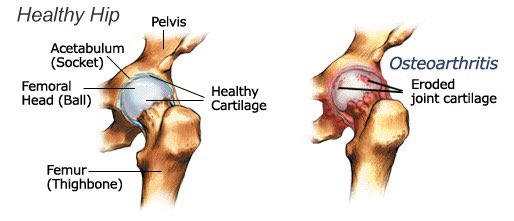

مفصل الورك يتكون من راس عظمة الفخذ المدور (femoral head) ويغطى بواسطة عظمة الحق والحوض(acetabulum)

وتبدأ عملية الخشونة والاحتكاك عندما تبدأ طبقة الغضروف المبطن بالتآكل عندها تبدأ عملية التهاب كبسولة المفصل وتكون التشوهات المصاحبة ويبدأ تضيق المفصل في الاشاعة السينية ونلاحظ احتكاك عظمة الفخذ بعظمة الحق